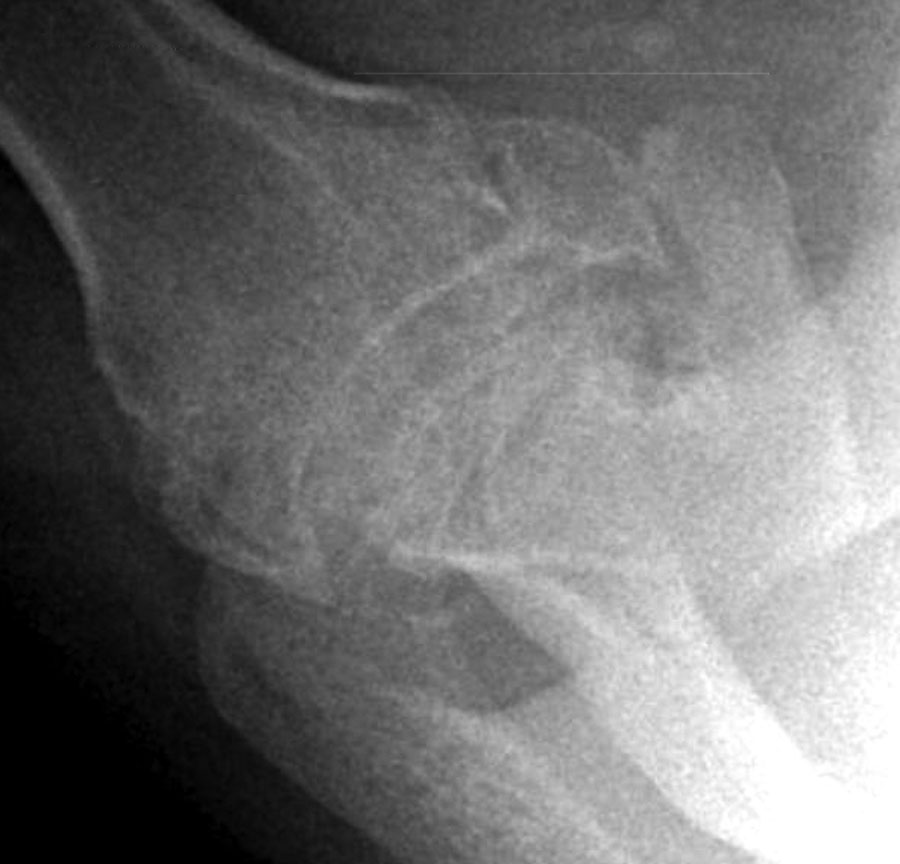

Learning Radiology avascular, necrosis, avn, shoulder What Does Avascular Necrosis Look Like On X Ray The present study provides a brief review of the main radiological aspects of the various forms of avascular necrosis, illustrated on the basis of a. Avascular necrosis occasionally appears as an area of abnormal signal involving the femoral head, neck, and intertrochanteric region. Knowing whether the condition is in its. If you are diagnosed with avn of the hip, your. What Does Avascular Necrosis Look Like On X Ray.

UW Shoulder and Elbow Academy Avascular necrosis of the shoulder, x What Does Avascular Necrosis Look Like On X Ray The present study provides a brief review of the main radiological aspects of the various forms of avascular necrosis, illustrated on the basis of a. Avascular necrosis (avn), also known as osteonecrosis, is most common in the femoral head. Historically, the terms ischemic and avascular necrosis were typically reserved for subchondral (epiphyseal) osteonecrosis, whereas bone. Osteonecrosis, also known as aseptic. What Does Avascular Necrosis Look Like On X Ray.